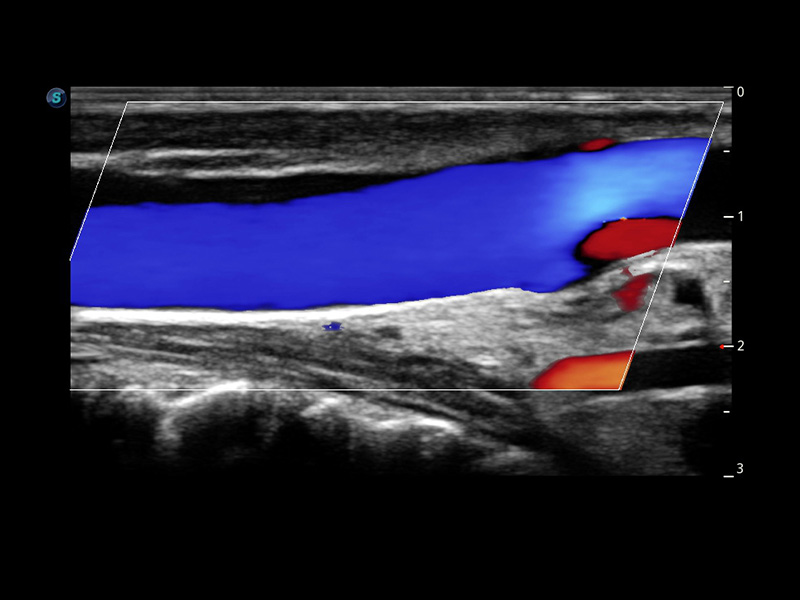

CEUS

Sfrutta il pieno potenziale dell'imaging a micro flusso

Il pacchetto completo di imaging ecografico e quantificazione con mezzo di contrasto di P60 offre ai medici una soluzione completa per valutare le dinamiche di perfusione in un'ampia gamma di ambiti clinici.

• Nodulo tiroideo maligno con CEUS

• Colestasi ostruttiva con MFI

• HCC con modalità mista

• HCC con MFI-Time

• CEUS con curva TIC